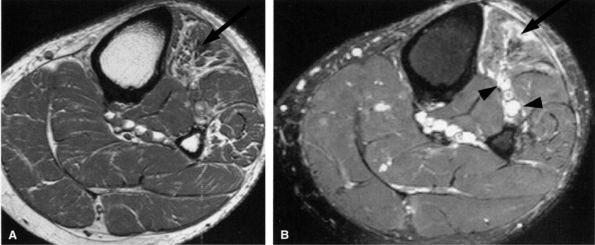

FIGURE 6.30 ● Common peroneal neuropathy with denervation atrophy and edema secondary to varicosities. (A) Axial T1-weighted image demonstrates denervation atrophy of the anterolateral muscles, predominantly the anterior tibial muscle (arrow). (B) Axial T2-weighted image depicts varicosities (arrowheads) next to the peroneal nerves and denervation edema of the anterior tibial muscle (arrow).

FIGURE 6.31 ● Surgically proven common peroneal neuropathy and denervation secondary to a hypertrophied biceps femoris muscle. (A) Axial T1-weighted image showing the common peroneal nerve (arrow) entrapped between a hypertrophied short head of the biceps femoris muscle (white asterisk) and the lateral head of the gastrocnemius muscle (black asterisk). (B) Axial T2-weighted fat-suppressed image displaying denervation edema in the anterolateral compartment muscles (arrows).